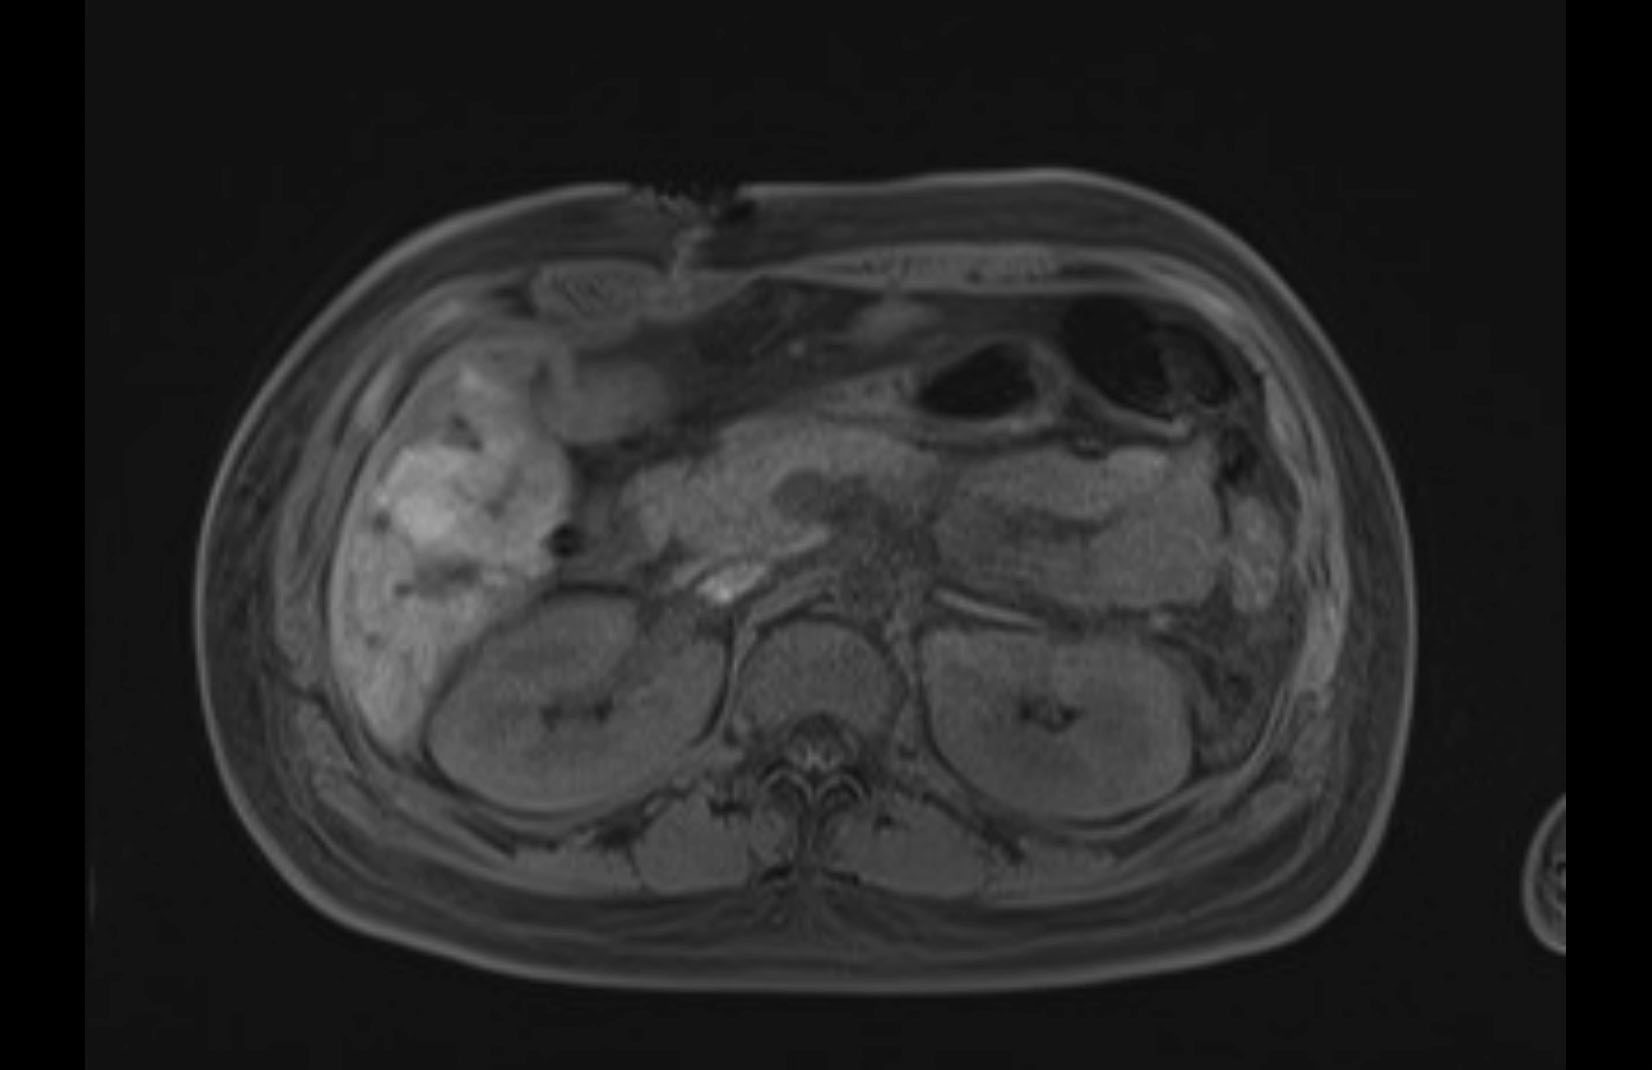

MRI T1

MRI T2